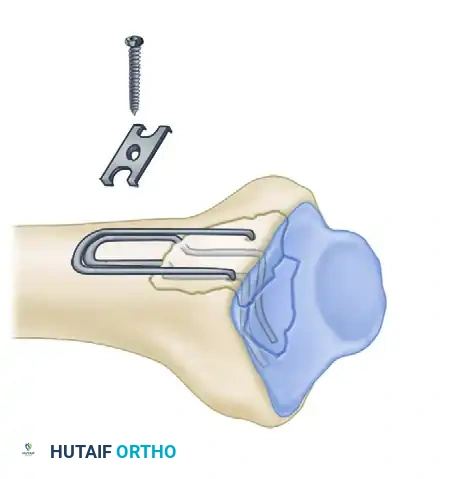

Biomechanics of Pin-Plate Fixation

Traditional radial styloid Kirschner wire fixation provides only a single point of constraint. This single point of fixation acts as a pivot, failing to prevent settling, bending, or radial drift of the distal fragments under physiological loads.

By adding a small buttress plate to the radial styloid pin, the construct is transformed. The pin-plate provides two distinct fixation points: the first through the distal end of the plate, and the second through the intact medial radial cortex. This dual-point constraint prevents collapse, resists dorsal torque, and halts radial migration.

Fragment-Specific Implants and Application

1. The Radial Pin-Plate:

Applied to the radial column, this implant enhances stability by providing a radial buttress. It effectively neutralizes bending forces that would otherwise cause the radial styloid to displace proximally and radially.